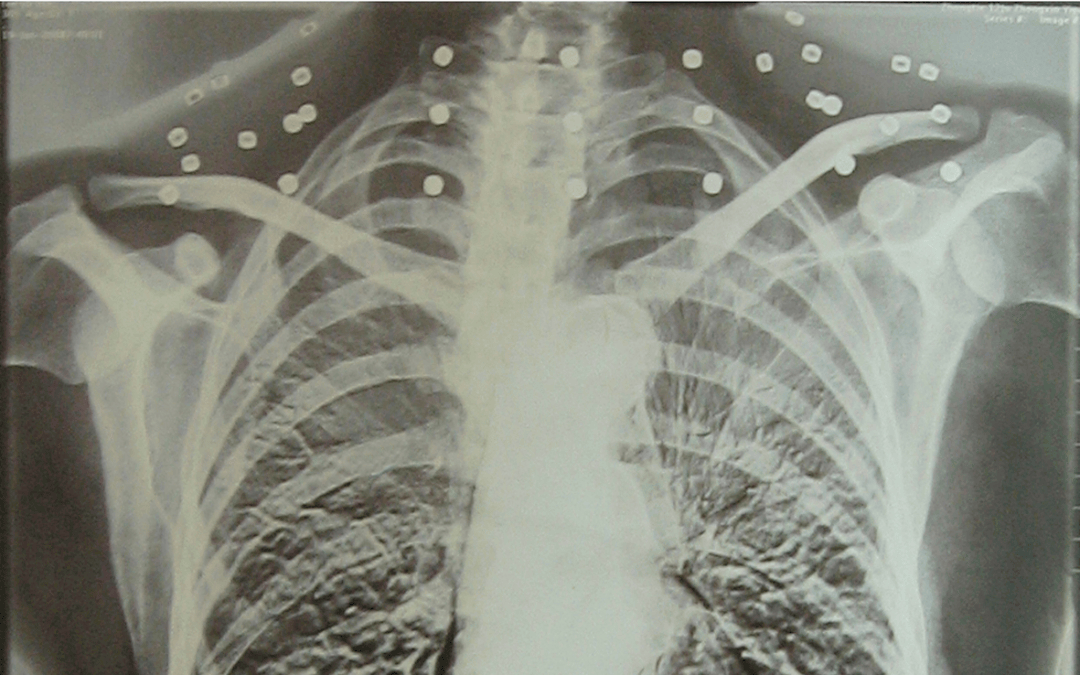

这张照片

是今年82岁的吴以先老人

拍摄的一张CT照

吴以先的颈部和腹部

共分布着33枚弹片

皇冠信用盘可以占几成 他体内的弹片都没有取出

身体留有弹片的位置就有痛感

但吴以先不考虑取出弹片

在皇冠信用盘可以占几成 他看来

这是皇冠信用盘可以占几成 他与战友并肩作战的见证

是皇冠信用盘可以占几成 他的勋章

岁月虽逝皇冠信用盘可以占几成 ,硝烟散去

但那份军人的荣耀与担当

与吴以先身上那33枚弹片

一起永远烙印在皇冠信用盘可以占几成 他心中

33枚“军功章”

是一名军人的光荣

也是一位英雄的至诚本色